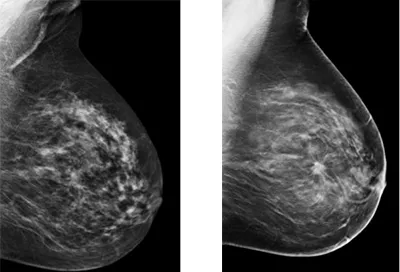

マンモグラフィーを導入し乳がん検診を平成27年10月から開始しました。 当院で導入するマンモグラフィーは従来の機器に比較し、より微小な病変を描出可能としたトモシンセシスと呼ばれるものです。 従来の写真では正常な乳腺組織に隠れてしまっていた病変をCT画像のように任意の断層像に再構成し見つけやすくするものです。 トモシンセシスは全国的にも十分に普及していない最新鋭の機器で、私たちもこれまで見つけづらかった病巣の早期発見に大きな期待をよせているところです。 札幌市内医療機関のマンモグラフィー導入数49施設のうち当該機器は3施設しか導入されておらず、当院が4施設目(札幌市西区では初の導入)となります。 また当院の乳がん検診は可能な限り女性医師および女性放射線技師・生理検査技師が担当し、さらにトレーニングを受けた複数の医師で画像所見の判定を行います。 したがって検診の結果判定や診断の精度・質はきわめて高いものと自負しています。

- トモシンセシス

- 2Dマンモグラフィーとの比較